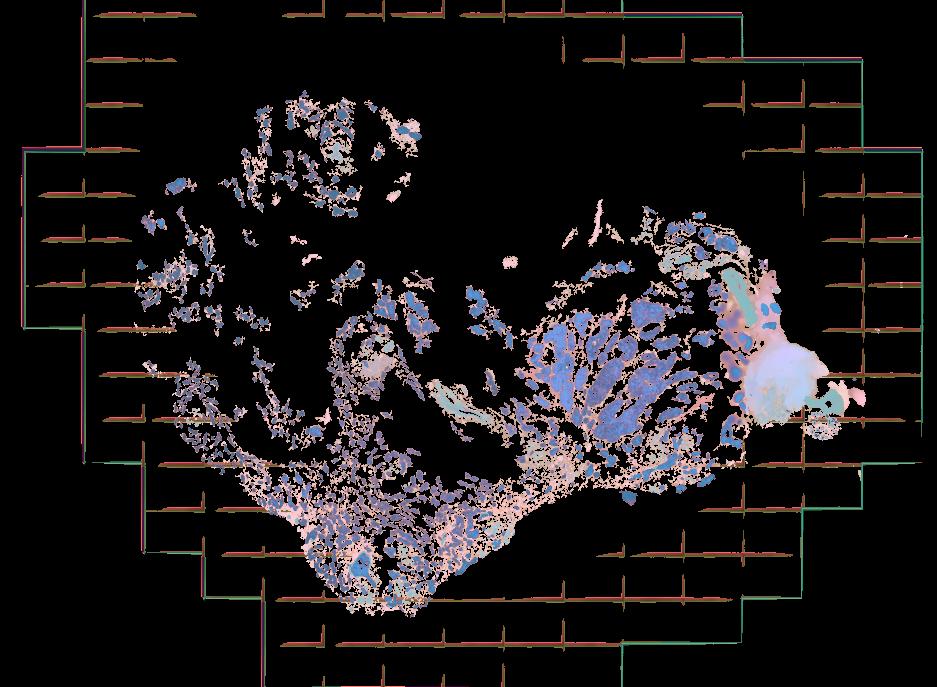

Atlas: Washington University

Breast cancer (BC) is defined by distinct molecular subtypes with different cells of origin. The transcriptional networks that characterize the subtype-specific tumor-normal lineages are not established. In this work, we applied bulk, single-cell and single-nucleus multi-omic techniques as well as spatial transcriptomics and multiplex imaging on 61 samples from 37 patients with BC to show characteristic links in gene expression and chromatin accessibility between BC subtypes and their putative cells of origin. Regulatory network analysis of transcription factors underscored the importance of BHLHE40 in luminal BC and luminal mature cells and KLF5 in basal-like tumors and luminal progenitor cells. Furthermore, we identify key genes defining the basal-like (SOX6 and KCNQ3) and luminal A/B (FAM155A and LRP1B) lineages. Exhausted CTLA4-expressing CD8+ T cells were enriched in basal-like BC, suggesting an altered means of immune dysfunction. These findings demonstrate analysis of paired transcription and chromatin accessibility at the single-cell level is a powerful tool for investigating cancer lineage and highlight transcriptional networks that define basal and luminal BC lineages.